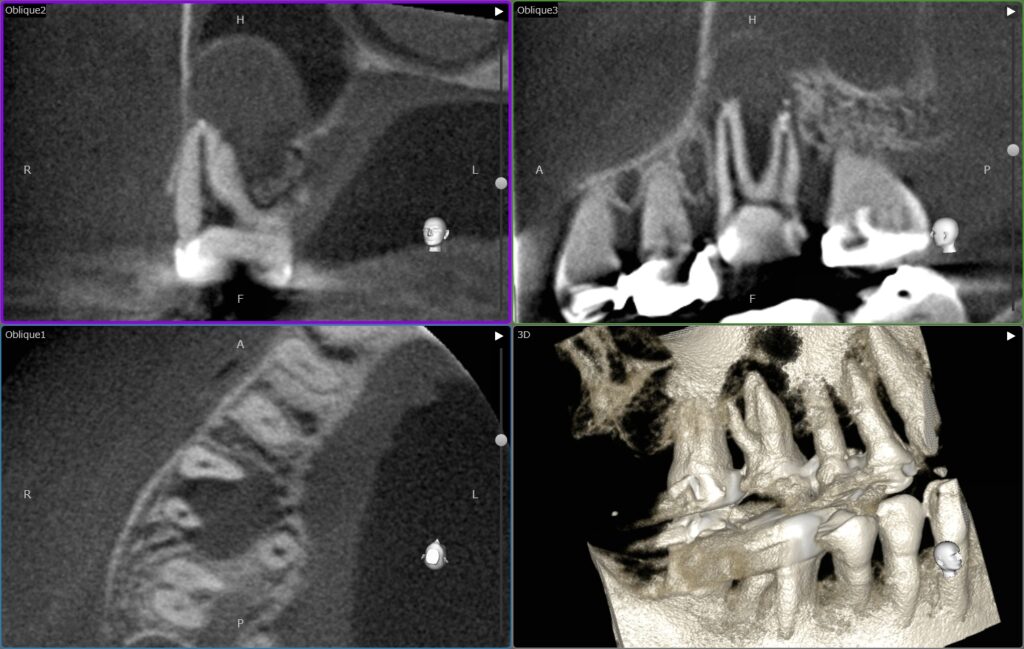

かかりつけの歯科医院にて、根の問題によって骨の吸収が大きく、治療が難しいと説明を受けられた患者様です。噛むと鈍い痛みがありCTを撮影したところ、上顎臼歯の根の先の病変が大きく、隣接する上顎洞(鼻の横の空洞)の骨が大きく失われている状態でした。根の治療によって回復の見込みがあるかどうか、治療の成功率などについてお話しいたしました。

2週間前に、噛むと鈍い痛みがありかかりつけの歯科を受診し、レントゲンとCTを撮影しました。その結果、根の先の膿が大きく骨が大きく溶けてしまっており、状態がかなり悪いと説明を受けました。特に、上顎洞という空洞の底の骨がなくなってしまっているため、基本的には抜歯が良いのでは?とのことでした。

ありがとうございます。先ほど撮影いたしましたCTを拝見したところ、確かに根の先の膿が大きく、骨が完全になくなっている状態です。ただ、歯を残せる可能性は十分に残っていると思います。

現在、神経の検査も行いましたが、まず歯の中の神経は完全に死んでしまっている状態です。そして、根の中の細菌がどんどん増えていくにつれて、根の先の周りの骨も溶かしてしまっています。ただ、このような場合、治療の成功率はおおよそ90%程度と報告されています。つまり、10本中9本は、治療によって骨が回復してくれるということです。

はい。歯の周りの骨の吸収が根の問題によるものであれば、根の治療で治癒すると骨も元のレベルにまで回復してくれます。ただし、現在の状況をみるととても吸収が大きいので、回復するまで1年近くかかることが予想されます。それまでは、固いものを噛まないことや、指や舌で押さえたりしないことが大切です。

奥歯の大臼歯は、根の先が上顎洞といわれる鼻の横の空洞と交通していることが多くあります。今回の⚫️⚫️様の右上の奥歯も同様です。歯が原因で根の周りで膿がたまると、上顎洞へその炎症が波及します。それによって、鼻がつまる、重い鈍痛がある、というような症状へつながります。根管治療を行うことで、上顎洞の炎症も軽減してきますので、ご安心ください。